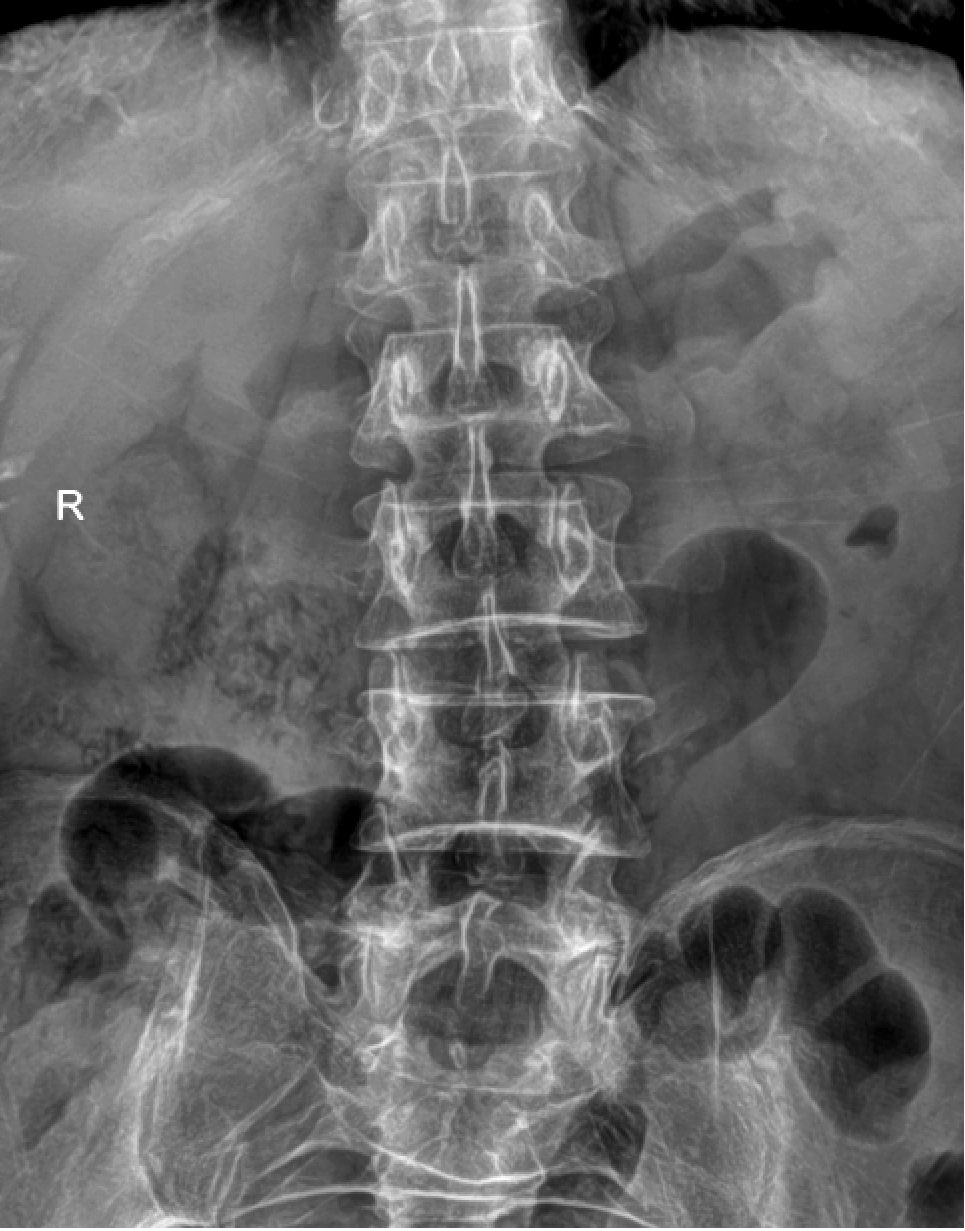

DR是最常用的X线检查技术,它是利用X射线的穿透能力生成从黑到白不同灰度的影像,也就是大家常说的“拍片”。

检查应用范围:骨骼系统、呼吸系统、循环系统、消化系统、泌尿系统等

优点:辐射剂量小,价格相对便宜,是疾病初筛的主要检查方式及骨关节系统的重要检查方法。

缺点:只能提供二维的平面影像,组织前后重叠且密度分辨率低,有些部位是看不见的,若需进一步观察,需要进行升级版的CT检查。

DR和CT是两种不同的检查方法,其侧重点不同,各具优势,两者不能互相替代。比如对于骨折来说,DR诊断要比CT更好,因为DR可以直接排除绝大多数的骨折,但是对于隐形性的骨折,CT会更好一些,可以作为DR检查后的进一步定性检查方法。